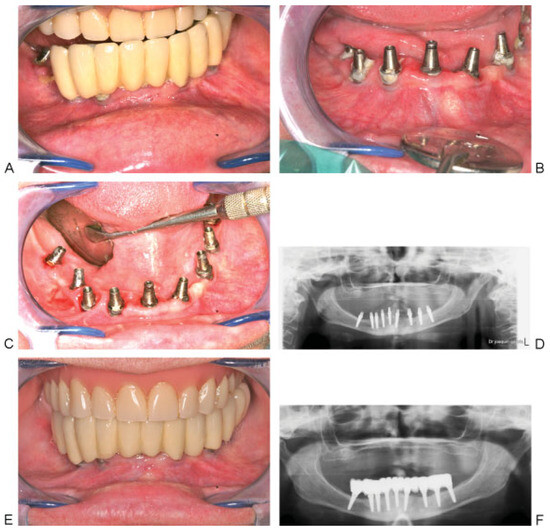

Figure 6. (A and B) Position and angulation of implants, noting the posterior implants where the inferior alveolar nerve was lateralized in both sides. (C) Final ceramometallic fixed prosthesis delivered 3 months postoperatively. (D) Orthopantomogram with the final restoration in place.

The postsurgical therapy protocol consisted of injecting the patient with the methylprednisolone sodium succinate 125 mg and Lincomycin 600 mg mixture for 2 days after surgery, together with ibuprofen 600 mg twice daily for 3 days. A soft diet and appropriate oral hygiene were prescribed for 2 weeks, including rinsing with 0.2% chlorhexidine gluconate twice daily. The sutures were removed 10 days after the operation without any postoperative complication. At 12 weeks, impressions were made for the fabrication of the final ceramometallic fixed denture, which was completed using conventional fabrication and prosthetic techniques. It was fabricated in three parts; the anterior four implants and the left side received screw-retained prosthesis, while the right side received cement-retained prosthesis (Figure 6).